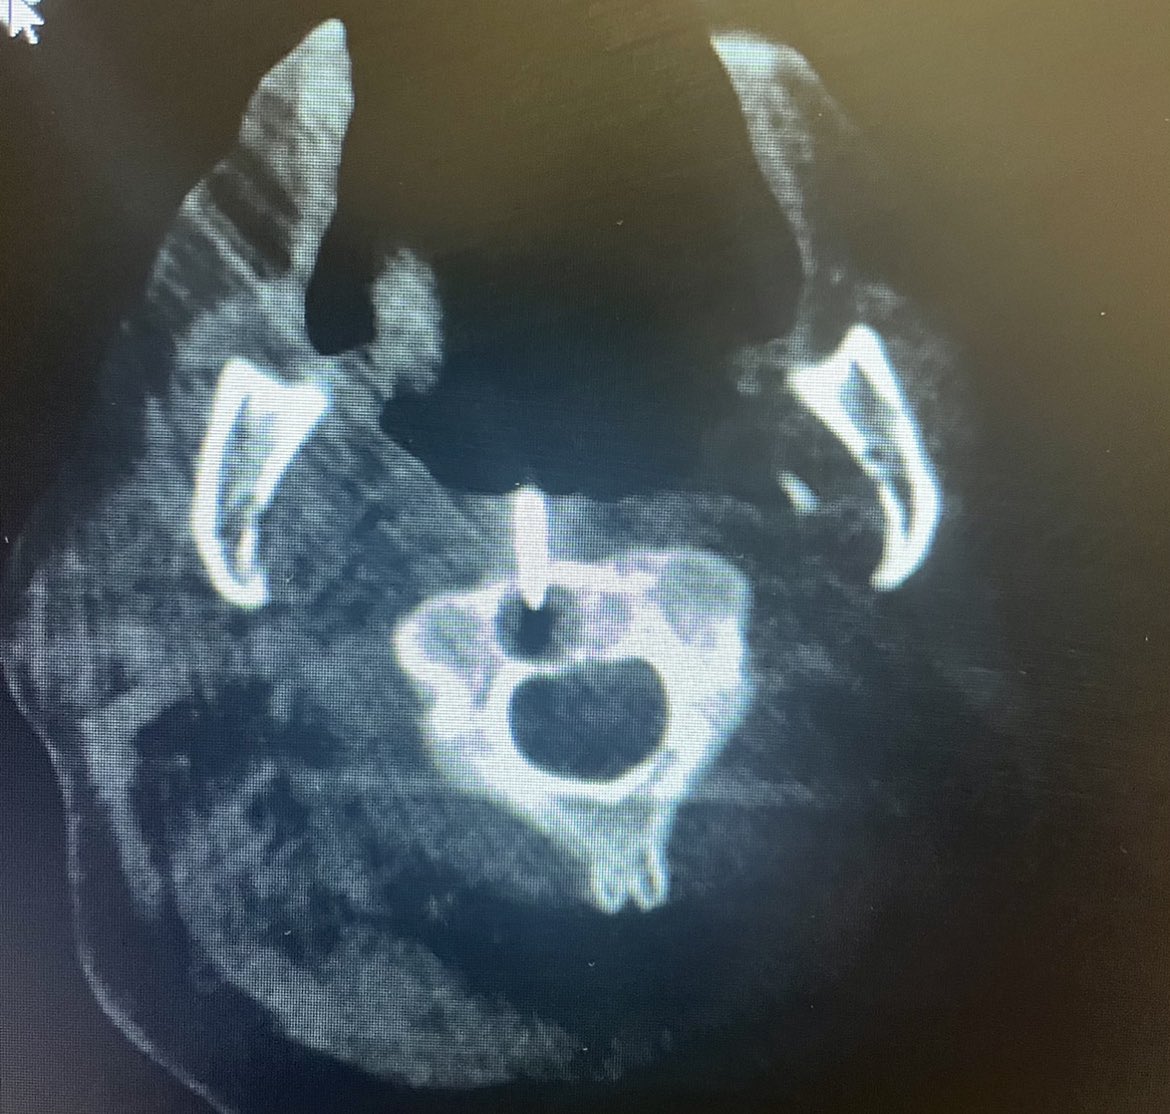

.@LucasRCmd, MPH; @HiroSparks, MD; Kara E. Masterson, MSN, NP; Scott J. Genshaft, MD; @AdamPlotnik, MD; and Siddharth A. Padia, MD, contributed to this open access article. See what they've been working on! brnw.ch/21wPx6v